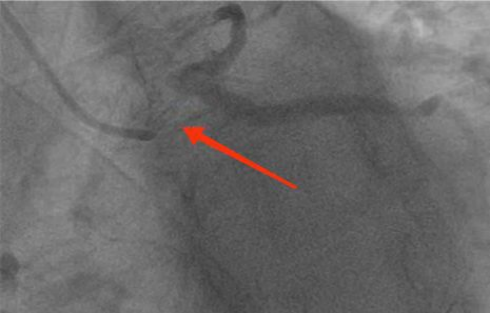

入院后我们完善检查,一些结果回示:CT(颅脑、胸部):左侧基底节区腔隙性梗塞灶或小软化灶可能。双肺未见明显异常。主动脉及冠状动脉壁钙化灶。腹部彩超:脂肪肝(轻度)。心脏超声:室间隔增厚;二尖瓣钙化;左室收缩功能测值稍降低。生化:总胆固醇6.93 mmol/L、甘油三酯2.59 mmol/L、低密度脂蛋白 4.93 mmol/L。空腹葡萄糖 6.49 mmol/L。糖化血红蛋白6.90 %。上述这些阳性结果意味着患者的心脏、颅脑、周围血管都受到不同程度损害,鉴于此,我们选择给林婆婆做冠状动脉造影,结果发现是“左主干病变”,图中所示左主干接近95%的狭窄,我们在操作过程当中,造影管稍微一碰到左冠脉开口,心电监护马上提示ST段抬高,压力崁顿,患者立马有胸痛、胸闷等症状。

(图示冠脉造影结果:左主干病变。箭头出无明显黑色造影剂通过,提示左主干开口、体部严重狭窄,只有一丝血流通过)